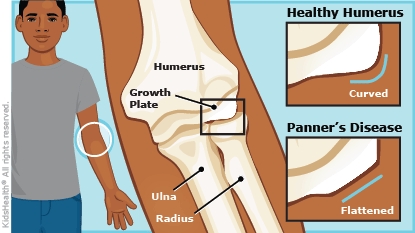

Panner’s disease happens from temporary changes in the capitellum. The capitellum is the outside bone of the elbow at the end of the upper arm bone (the humerus).

Panner’s disease is caused by stress on the capitellum and the surrounding cartilage. The stress is usually from repeated motions in sports, such as throwing in baseball or tumbling in gymnastics.